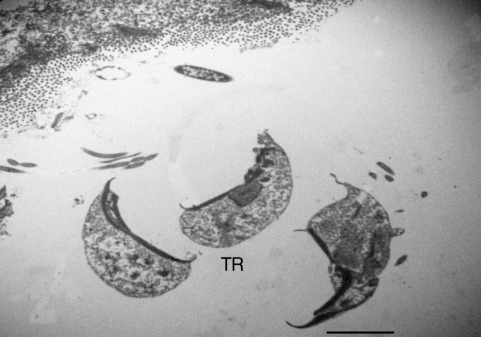

Growth retardation, depression, and chronic watery diarrhea were recorded for the affected turkey poult. In histological examinations, moderate enteritis characterized by blunting and fusion of villi, villous edema, an increase in lamina propria inflammatory cells, and increased number of mitotic figures in the crypt epithelial cells were noticed. Large numbers of flagellated conical protozoan were present within the lumen and intervillous spaces of the jejunum, ileum, and cecum (Fig. 1). Some of which seem to be firmly attached to the gut epithelial lining. In TEM studies on parasagittal sections, the trophozoites of the organism was a uninuclear, conical, or pyriform-shaped flagellated cell with a prominent ventral sucker-like disc (Figs. 2-4). There were sharp points at the posterior and anterior ends of the ventral sucker and 6 flagella emerging from an opening space of ventrodorsal surface of the parasite (Figs. 3, 4). In cross sections, the sucker seemed to be concave and had an electron dense free sharp edge. The morphological characteristics of the organism are in agreement to those described for Cochlosoma anatis.

Several TEM pictures of the parasite made us propose that the ventral sucker may be composed of a relatively rigid structure that partially maintains and supports the morphology of the trophozoite. The ventral sucker seems to be a plate-like structure with an electron-dense margin and a concave center which is composed of a modified cytoplasmic membrane. The cytoplasmic non-electron dense portion of the ventral sucker may have important physiological functions, for example, as a feeder organ of the parasite, and also may serve as an organ that irritates the mucosal epithelial cells. Perhaps, the ventral sucker enables the parasite to obtain its essential nutrients from the oozed or secreted materials coming from the site of attachment. Therefore, it is supposed that the ventral sucker may have specialized functions required for the protozoan survival and pathogenicity. Since the major sources of the organism are contaminated feed and litter, keeping birds in the free ran condition could facilitate transmission of the infection between susceptible birds.